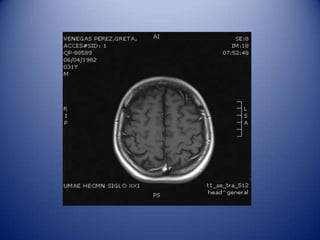

Identifying differential diagnosis

Embolic infarct.

Opportunistic infection.

Brain abscess.

NP SLE.

Brain tumor.

MRI Diagnosis

Radiology: Infarcts (embolus), cortical,

in two different territories, restricted

diffusion, low ADC.

Neurology: Opportunistic infection

(toxoplasmosis) vs. brain abscess

MRI in NP SLE

Multiple white matter lesions.

Cerebral infarction.

Cerebral hemorrhage.

Venous sinus thrombosis.

Atrophic changes.

Spinal cord disease.

Identifying differential diagnosis Embolicinfarct. Opportunistic infection. Brain abscess. NP SLE. Brain tumor.

• 18.

MRI Diagnosis Radiology: Infarcts(embolus), cortical, in two different territories, restricted diffusion, low ADC. Neurology: Opportunistic infection (toxoplasmosis) vs. brain abscess (headache, fever, seizures).